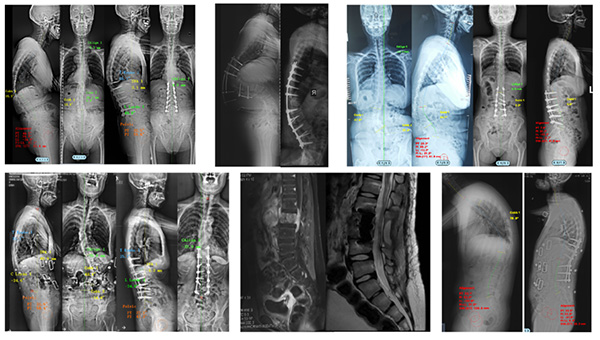

本中心以精湛的医疗技术和丰富的临床经验著称,所治疗的疾病种类覆盖了退行性变、肿瘤、先天畸形和慢性疼痛等几乎全部脊柱脊髓疾病。在常见脊柱脊髓疾病如颈椎病、腰椎病、椎管内肿瘤、脊髓空洞及慢性疼痛等的诊治中,秉持微创与安全理念,以显微镜、内镜、经皮通道等显微外科技术为引领,为患者提供安全有效的治疗方案。同时,本中心在高难度手术领域成果斐然,经口齿状突切除技术、显微镜下颈椎后纵韧带骨化前路椎管扩大技术(ACAF技术)、基于OLIF的脊柱畸形矫形、脊柱肿瘤(en bloc)切除联合3D打印椎体重建、髓内肿瘤、前路肠源性囊肿切除、脊髓与周围神经电刺激、脊柱畸形矫形技术以及脊柱截骨治疗脊髓拴系等复杂手术已成为常规操作,相关手术技术和开展例数在国内均处于领先地位。本中心医师创新性提出直接后路寰枢关节松解复位技术(PFDF技术)、微创蛛网膜下腔-蛛网膜下腔脑脊液搭桥术、时序脊髓电刺激联合外骨骼治疗等新技术,获得国际声誉。

手术效果